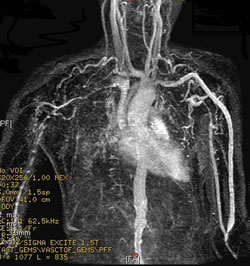

Tromboembolia Pulmonar: Se caracteriza por la formación de un coágulo que ocluye el riego sanguíneo de los pulmones que proviene de alguna parte del cuerpo, mas comúnmente de los miembros inferiores. Esto en los casos más severos puede ocasional fracaso del corazón derecho. Los síntomas son aparición súbita de dificultad respiratoria, baja de oxigeno en la sangre, taquicardia y ocasionalmente dolor en el tórax.

Vasculitis Pulmonar: Es una inflamación de los vasos sanguíneos del pulmón secundario a enfermedades sistémicas también de origen inflamatorio. Se caracteriza por dificultad respiratoria rápidamente progresiva, hemorragia pulmonar y baja de oxígeno en la sangre.